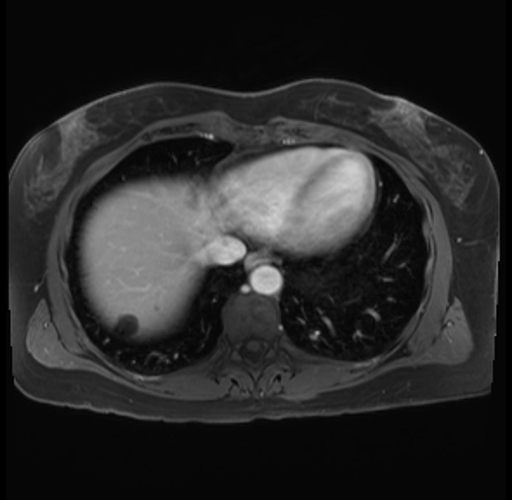

Imaging Analysis

Look through the patient's CT scan to identify any areas of concern for the necessary procedure.

Based on your CT findings, which issue(s) are present and would give reason for "planned slowing down moment(s)" in this case?

Considering a standard distal pancreatectomy procedure, what step(s) of the operation would you do differently in this case?